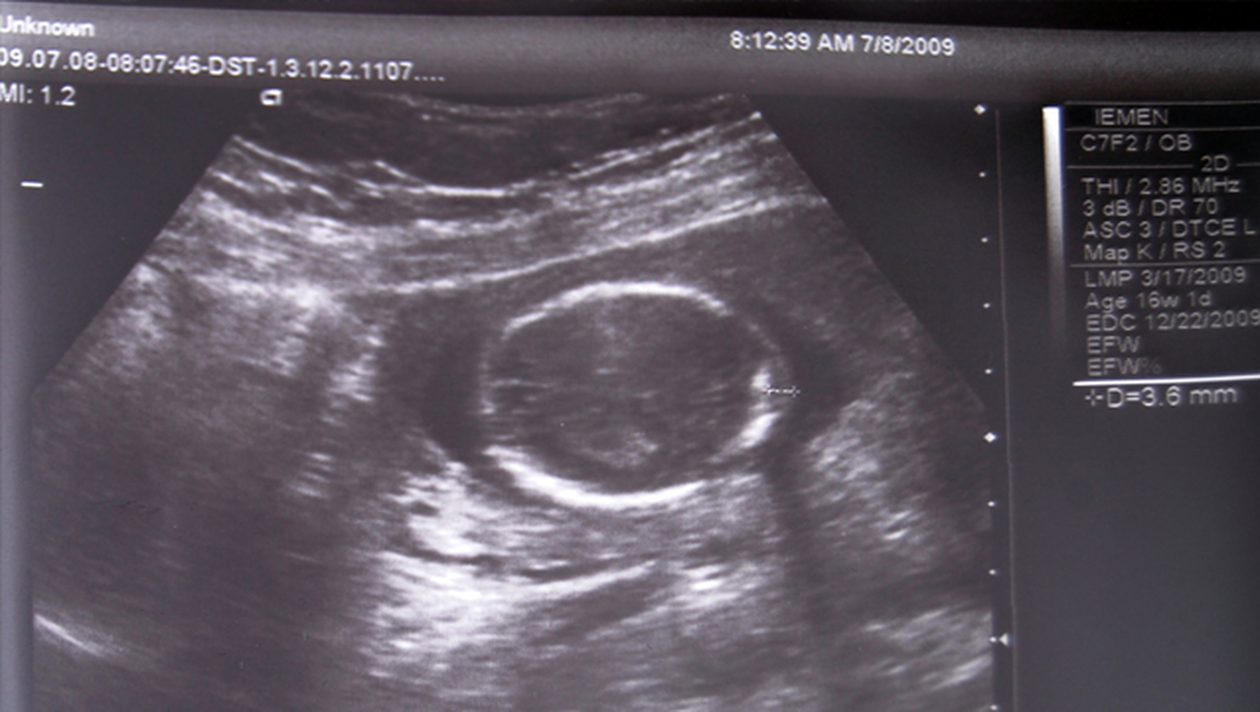

In prima faza, medicii au crezut ca femeia are un parazit in stomac, insa uimirea le-a fost mare cand au descoperit un fetus in burta sa. De-a lungul vremii, au fost identificate mai putin de 300 de astfel de cazuri. In urma unei ecografii, medicii au descoperit ca fetusul era calcifiat. Femeia urmeaza sa intre sub operatie pentru a i se scoate fetusul, compus din tesuturi moarte.